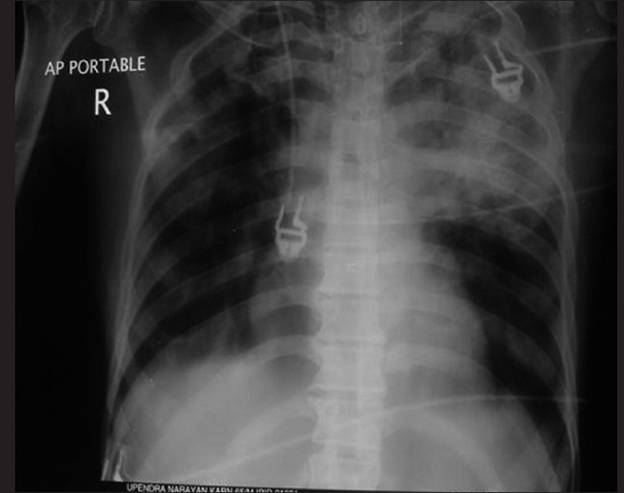

Hình ảnh X-quang ngực người này cho thấy tổn thương đông đặc đồng nhất ở thùy trái trên và lan sang các vùng mờ phế nang (alveolar opacities) trong các phần còn lại của phổi [Hình 1]. Hình ảnh siêu âm cho thấy sự tràn dịch màng phổi hai bên nhẹ và bụng ứ nước nhẹ cùng với lá lách phình.Không phát hiện thấy các tổn thương khu trú(focal lesions) và sự phình to bất thường của các cơ quan nội tạng.

Hình 1: Hình chụp X-quang ngực cho thấy tổn thương đông đặc ở thùy trái trên